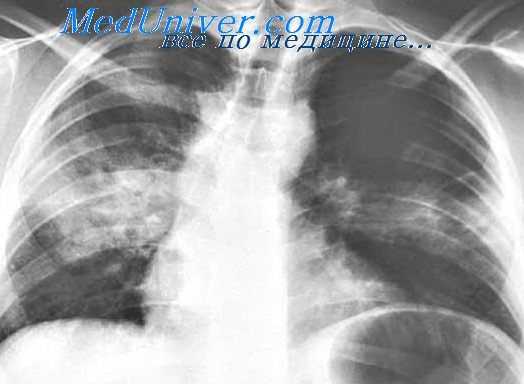

Методы исследования • Серологические методы •• РСК. Диагностический титр — 1:16–1:32 •• РТНГА. Диагностический титр — 1:512 и выше или 4-кратное нарастание титра АТ •• Реакция прямой иммунофлюоресценции •• Сыворотку крови для серологических реакций берут с интервалом в 2–3 нед, а для проведения РИФ — 3–4 нед. Повторный анализ — через 6–8 нед • Лабораторные методы. Общий и биохимический анализы крови — незначительный лейкоцитоз, увеличение СОЭ, повышение содержания печёночных ферментов в сыворотке крови, эозинофилия • Обзорная рентгенография органов грудной клетки — интерстициальная пневмония в виде участков альвеолярной инфильтрации и маленьких узелков затемнения, долевое уплотнение лёгочной ткани (наблюдают редко), лимфаденопатия, иногда экссудативный плеврит.

На 3-5 сутки к общеинфекционным симптомам присоединяются признаки поражения легких: боли в грудной клетке, сухой, а затем продуктивный кашель со слизисто-гнойной мокротой. Рентгенологически определяются признаки интерстициальной, мелко- или крупноочаговой, долевой орнитозной пневмонии. К исходу первой недели заболевания увеличивается печень. Для орнитоза характерно поражение нервной системы с признаками нейротоксикоза: головной болью, адинамией, бессонницей, депрессией, при тяжелом течении – галлюцинациями, бредом, эйфорией. Возможно развитие серозного менингита с доброкачественным течением.

Орнитозная пневмония диагностируется с помощью физикального обследования и рентгенографии легких. При менингеальных симптомах проводится спинномозговая пункция с исследованием цереброспинальной жидкости. Возможно проведение и анализ внутрикожной аллергической пробы с инактивированной культурой возбудителя орнитоза. Дифференциальная диагностика направлена на исключение ОРВИ, гриппа, атипичной пневмонии, инфекционного мононуклеоза, бруцеллеза, лихорадки Ку, туберкулеза, легионеллеза, глубоких микозов (аспергиллеза, гистоплазмоза, нокардиоза, кокцидиоидоза).

Продолжительность заболевания зависит от тяжести течения. Обычно со 2-4-й недели температура начинает снижаться, происходит обратное развитие симптомов, но изменения в легких сохраняются до 30 дней и более, «сетчатость» легочного рисунка на рентгенограммах может выявляться до 2 мес. Период реконвалесценции сопровождается астенией, быстрой утомляемостью, иногда анемией, которые могут беспокоить реконвалесцентов 3-4 мес и более. В 10-20% случаев описаны обострения и рецидивы, ранние (на 2-4-й неделе заболевания) и поздние (через 3-6 мес).